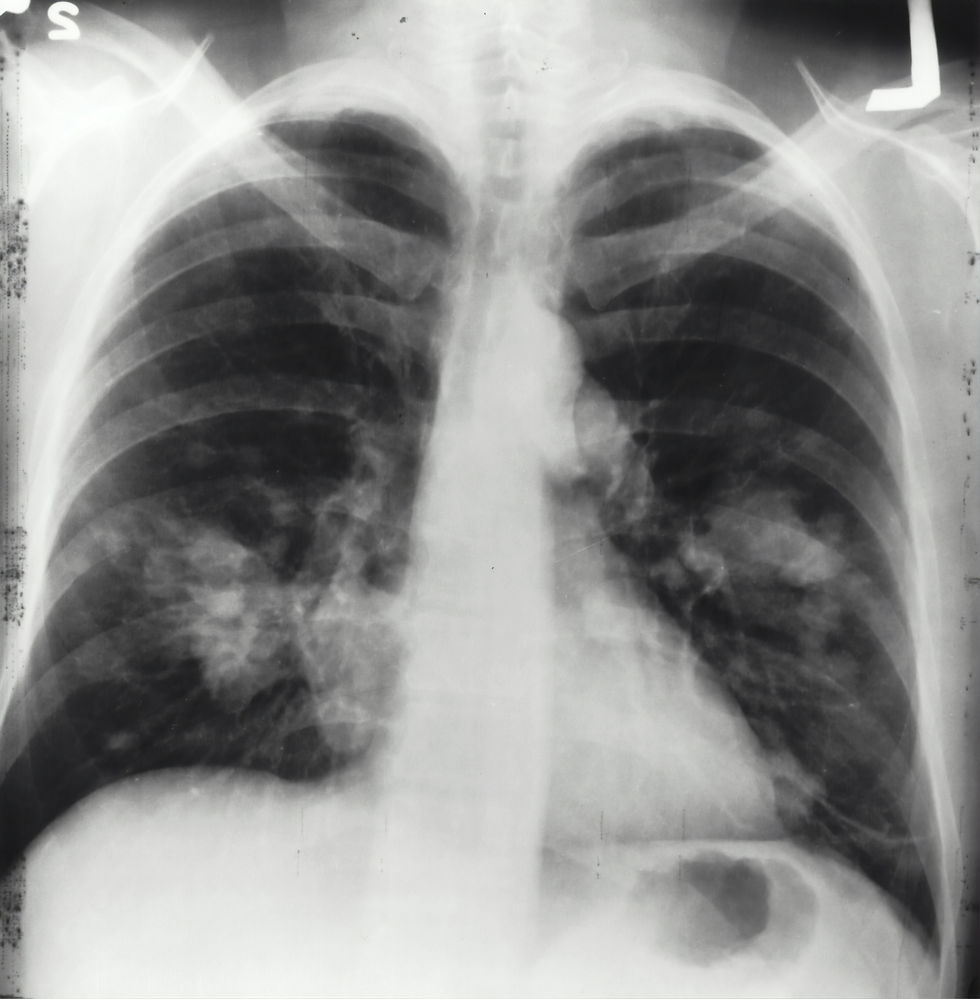

Ofrecemos una visión completa de las diversas especialidades médicas involucradas en la oncología, incluyendo la última investigación, tratamientos innovadores y consejos prácticos para la gestión del cuidado del cáncer.